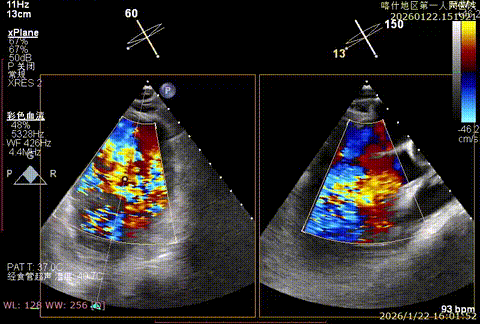

该例患者为VFMR,术前制定手术策略:患者二尖瓣重度反流,后叶严重栓系,心房心室扩大。患者瓣口面积4.5cm2,预计使用两枚XTR解决患者瓣叶脱垂和反流。考虑到先于2区进行钳夹,应该能获得足够的房间隔穿刺高度。术中经不断调整穿刺位点,最终穿刺高度4.4cm。成功穿刺后将第一枚XTR送入二尖瓣正上方,进行弹道测试Orientation调整后,最终定位于2区正上方下左心室。第一枚夹子在左室成功捕捞和钳夹瓣叶后,瓣叶反流程度显著降低,夹子外侧仍见部分反流,随后在第一枚夹子外侧再次放置一枚XTR,瓣叶反流程度进一步降低至微量。通过TEE观察,二尖瓣双孔组织桥稳定,跨瓣压差3mmHg,肺静脉逆流改善明显,手术安全结束。

X-plan重度反流

3D enface观察反流